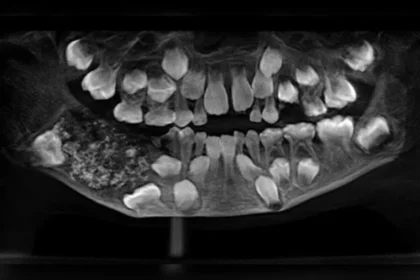

Menino de 7 anos tem 526 dentes retirados em cirurgia

O que parecia apenas um inchaço no maxilar de um menino de…